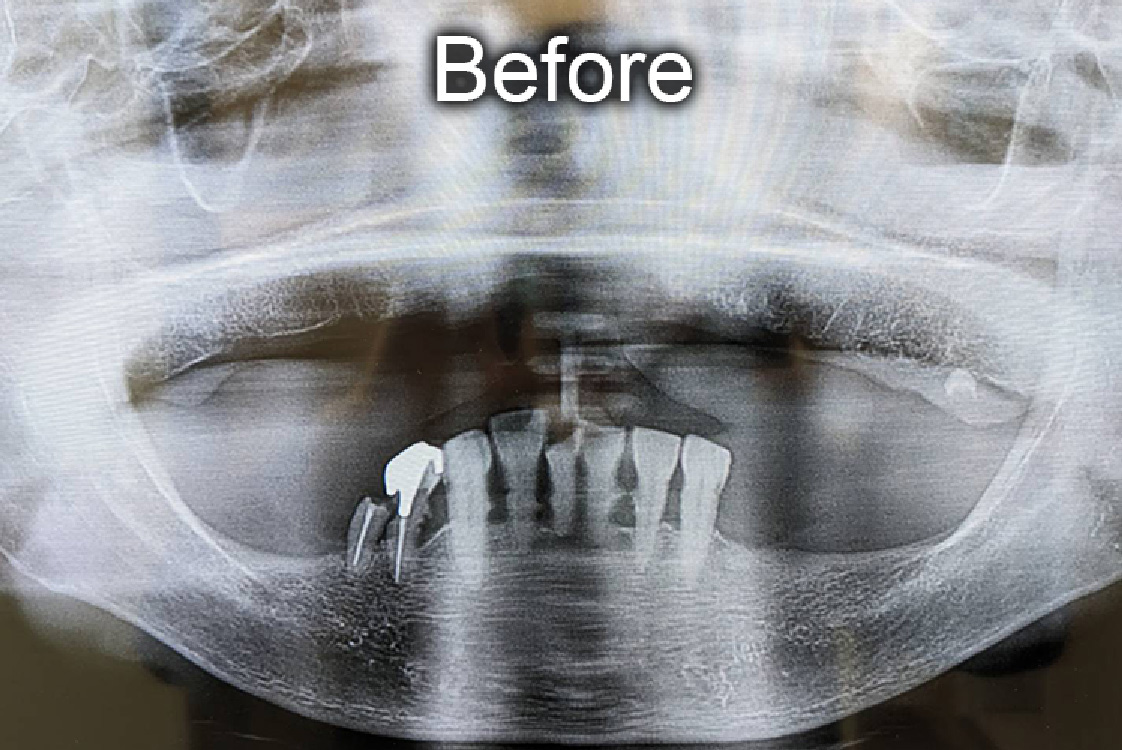

■ 治療内容

残存歯が8本の患者さん、日常生活で入れ歯を使用。食事や私生活で苦労が多かっため、歯を固定できるインプラント治療を選択。

上顎6本・下顎4本、計10本のインプラント埋入し、ジルコニアセラミッククラウン製の歯列を装着。 -